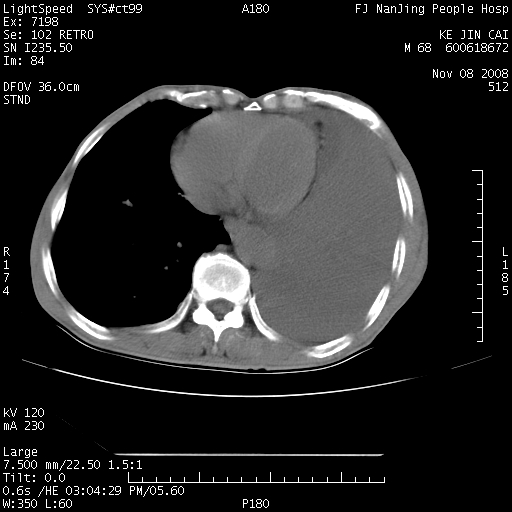

是个很有看头的病例,咋人气那么不旺?没多少人兴趣呢?这个病例几大怪:1   恶性肿瘤侵犯心肌左房怪,心肌一般不会被恶性肿瘤侵犯吧?2   左下肺均匀实变怪,内无含气,有别一般不张实变,含气肺泡完全为液体取代,而非一般不张实变的肺萎陷,冷不丁还以为是肿大的脾脏3   肿瘤本身怪,像tb肺不张4   这么有看头的病例没人气怪。呵呵。

左肺恶性肿瘤侵犯肺动脉,左心房内瘤栓,胸膜转移。